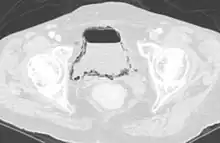

Cystite compliquée d'un emphysème

La pneumaturie désigne la présence d’air dans l’urine, ce qui est toujours anormal.

La principale cause de pneumaturie est la présence d’une fistule uro-digestive (souvent retrouvée lors d'une diverticulite du sigmoïde).